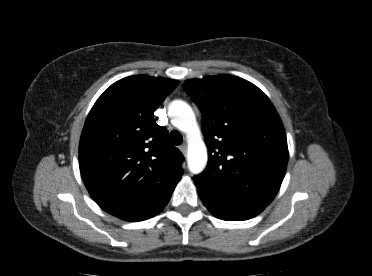

Мультиспиральная компьютерная томография – это современный высокоинформативный рентгенологический метод диагностики различной патологии легких. КТ основана на применении рентгеновского излучения. Однако в отличие от обычного рентгена, при котором снимки делаются в одной плоскости и изображения органов могут накладываться друг на друга, КТ лишена этих недостатков, так как во время компьютерной томографии сканирование проводится в различных плоскостях.

Во время исследования рентгеновская трубка томографа вращается вокруг исследуемой области и производит множество послойных снимков с шагом 0,5-1 мм. Полученные снимки поперечного сечения с помощью компьютерной программы могут быть преобразованы в 3D-изображения исследуемого органа или участка ткани. Это позволяет выявлять практически все заболевания легких на ранних стадиях и назначать своевременное лечение.

В некоторых случаях, например, при подозрении на опухолевый процесс, проводится КТ легких с контрастированием, когда для лучшей визуализации патологического очага пациенту внутривенно вводится йодсодержащий контрастный препарат. Контрастное вещество накапливается в патологических участках и обеспечивает их яркую визуализацию на фоне неизмененной ткани. С помощью контрастирования можно визуализировать кровеносные сосуды, выявить первичные опухоли и метастазы в легких, дифференцировать новообразования, например, отличить доброкачественную опухоль от злокачественной.